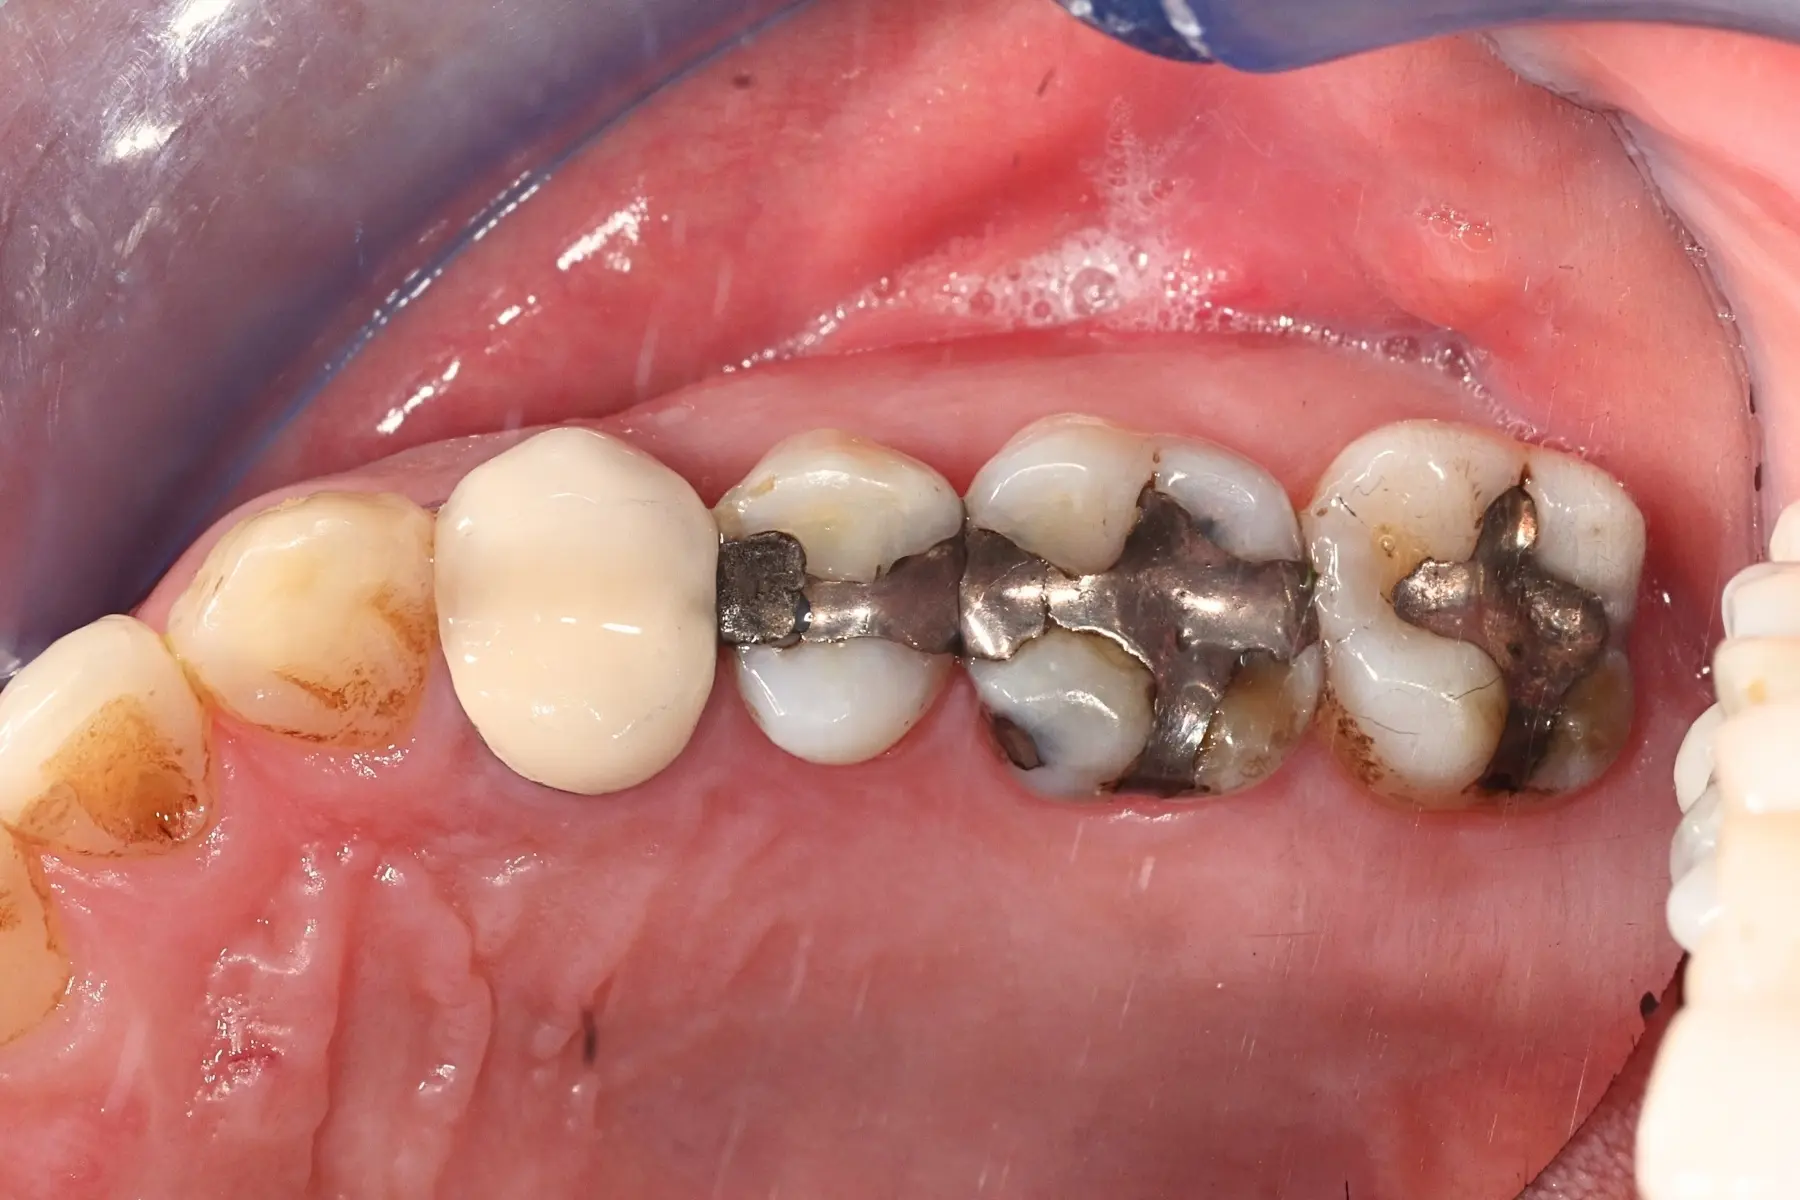

• 術前 43

術後 41

牙橋

主治醫師

• 楊明憲

治療時間

約1年4個月

主訴

吃東西左邊後牙會痛